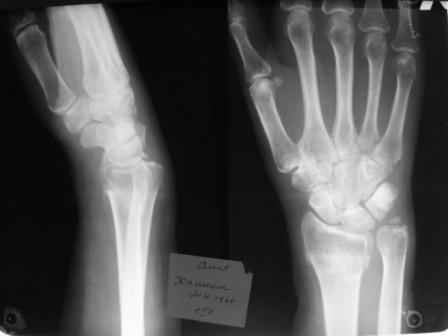

Уважаемые коллеги.Прошу обсудить случай лечения перелома дистального метаэпифиза лучевой кости. Ситуация скандальная и крайне неблагоприятная. Больная с патологической обстоятельностью мышления, склонностью к сутяжничеству, патологическими умозаключениями, не поддающимися коррекции (см. психиатрию, правда офиц. диагноза нет). В данном случае есть ряд ошибок с нашей стороны, прежде всего в отношении качества ведения документации (за что получил административное взыскание, по делом мне дураку). В остальном- придерживались в лечении подхода классический советской школы. Так как умную операцию…… сами знаете… 15.12- перелом луча в Москве. Там же репозиция, гипс. Дальнейшее лечение у нас в ЦРБ. 20.12.- вторичное смещение в гипсе21.12- под внутривенным наркозом- репозиция, гипсовая лонгета. Дальше начинается самое интересное. После репозиции больная заявила, что я (репозицию делал я) порвал ей все связки в суставе, посинел у нее 5 палец, якобы я за него тянул и т. д. На самом деле на 2 сутки после репозиции рука немного отекла и было незначительное сдавление гипсом, который был ослаблен. Дальнейшее лечение консервативное. Через 6 недель- гипс снят, назначено ЛФК. Пациентка крайне недовольна. Говорит, что на снимке у нее выступает кость, я ей сломал руку и.т.д. В общем началось. Пациентка прочитала в интернете наверное все, что есть по данной травме.По заключениями рентгенологов и консультанта из КДЦ областной больницы - стояние отломков допустимое. Объективно говоря- снижена высота лучевой кости, диастаз лучелоктевого сочленения, и не сросся шиловидный отросток. однако на РКТ при сравнении с другой стороной- разница незначительная. Дальше в одной из больниц нашей области и одной из больниц Москвы (вроде бы КГБ 53) врачи сказали, что репозиция сделана плохо. Нужна операция (восстановить длину лучевой кости), даже один из них предложил РЕДРЕССАЦИЮ (хи-хи) с наложением аппарата Илизарова. Что это для данной больной- радость неописанная. (см. описание психического статуса). Ничем другим, кроме зарабатывания дешевого авторитета объяснить данный факт не могу.Кстати, у больной еще нейропатия локтевого нерва.Для разрешения конфликта больная направлена на консультацию в ЦИТО на 03.03.11.

Заключение: Консолидированный в неправильном положении перелом дистального метафиза левой лучевой кости. Ротационная контрактура левого предплечья. Рекомендовано- разработка, консультация через 2 месяца.

Объективно: пронация почти полная, супинация ограничена, ладонная флексия около 20, тыльная 10. Гипостезия в зоне инервации локтевого нерва. Незначительный отек. Хват кисти полный. Сила 4 балла.

В общем, типичная картина раннего восстановительного периода после снятия гипса. Визуально конечность не изменена.

Мне кажется, что на самом деле, ситуация не стоит и выеденного яйца. При правильном лечении должно быть полное восстановление функции.